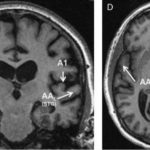

Study: Study of rare dementia shows selective attack on areas of brain — ...

Patients in a new Northwestern Medicine study were able to comprehend words that were written but not said aloud. They could write the...